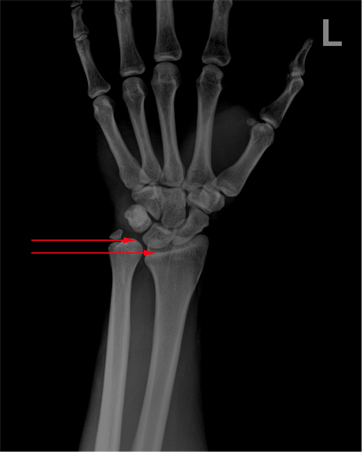

x-ray 사진